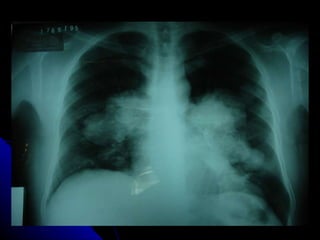

CANDIDIASIS